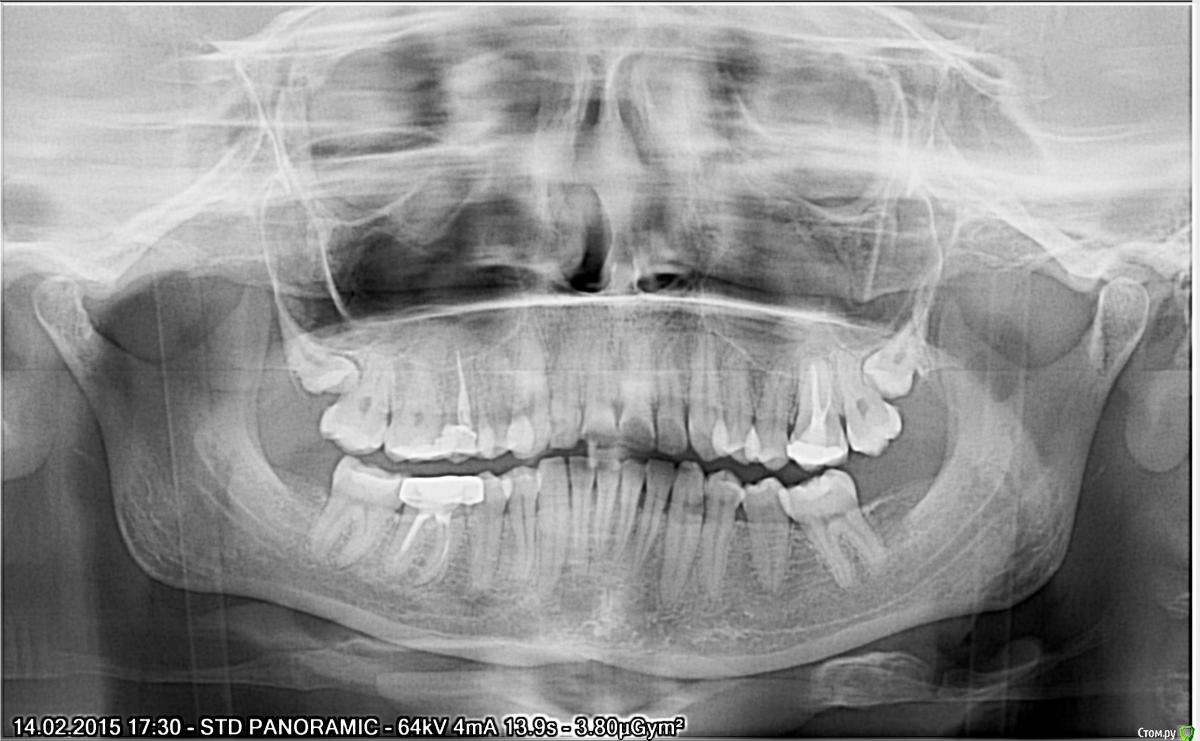

korsa Опубликовано 5 октября, 2016 Поделиться Опубликовано 5 октября, 2016 Всем добрый вечер, прошу помощи. Давным давно, уже и не помню где и кто делал, был удален нерв и запломбирован зуб. 3 недели назад обратилась к врачу с острой болью, не могу наступать, на горячее/холодное реакции нет. Терапевт не смогла вскрыть запломбированный канал и отправила в другую клинику. В другой, мне не стали вскрывать канал(почему не могу сказать, пазухи близко, наговорила мне что-то, для меня не ясное), выписала антибиотики и отпустила, сказав явиться через день. На следующий день зубная боль прошла, но случился сильный отек. На повторном приеме отправила меня к хирургу, та удивилась что канал не вскрыли при первом обращении. В общем, хирург поставила дренаж и отпустила. На 3 день, дренаж сняли, отправили на КТ. После КТ хирург сказала искать врача и попробовать лечить. Но т.к. я простыла, лечение отложилось на 10 дней. После выздоровления, я записалась на консультацию к другому хирургу... Проснувшись в день записи обнаружила снова отек щеки, не такой сильный как в первый раз, но отек(Помогите определить, пожалуйста, действительно он под удаление или все же можно спасти, зуб жевательный, да и вообще, со своим не хотелось бы расставаться(((Первый снимок от 20.09.16И еще, что за потемнение над зубом, такое обширное(под красной линией)Зуб - 26.Второй 14.02.15 - на нем то вообще ни чего нет. Ссылка на комментарий

korsa Опубликовано 13 октября, 2016 Автор Поделиться Опубликовано 13 октября, 2016 вот полный снимок Ссылка на комментарий